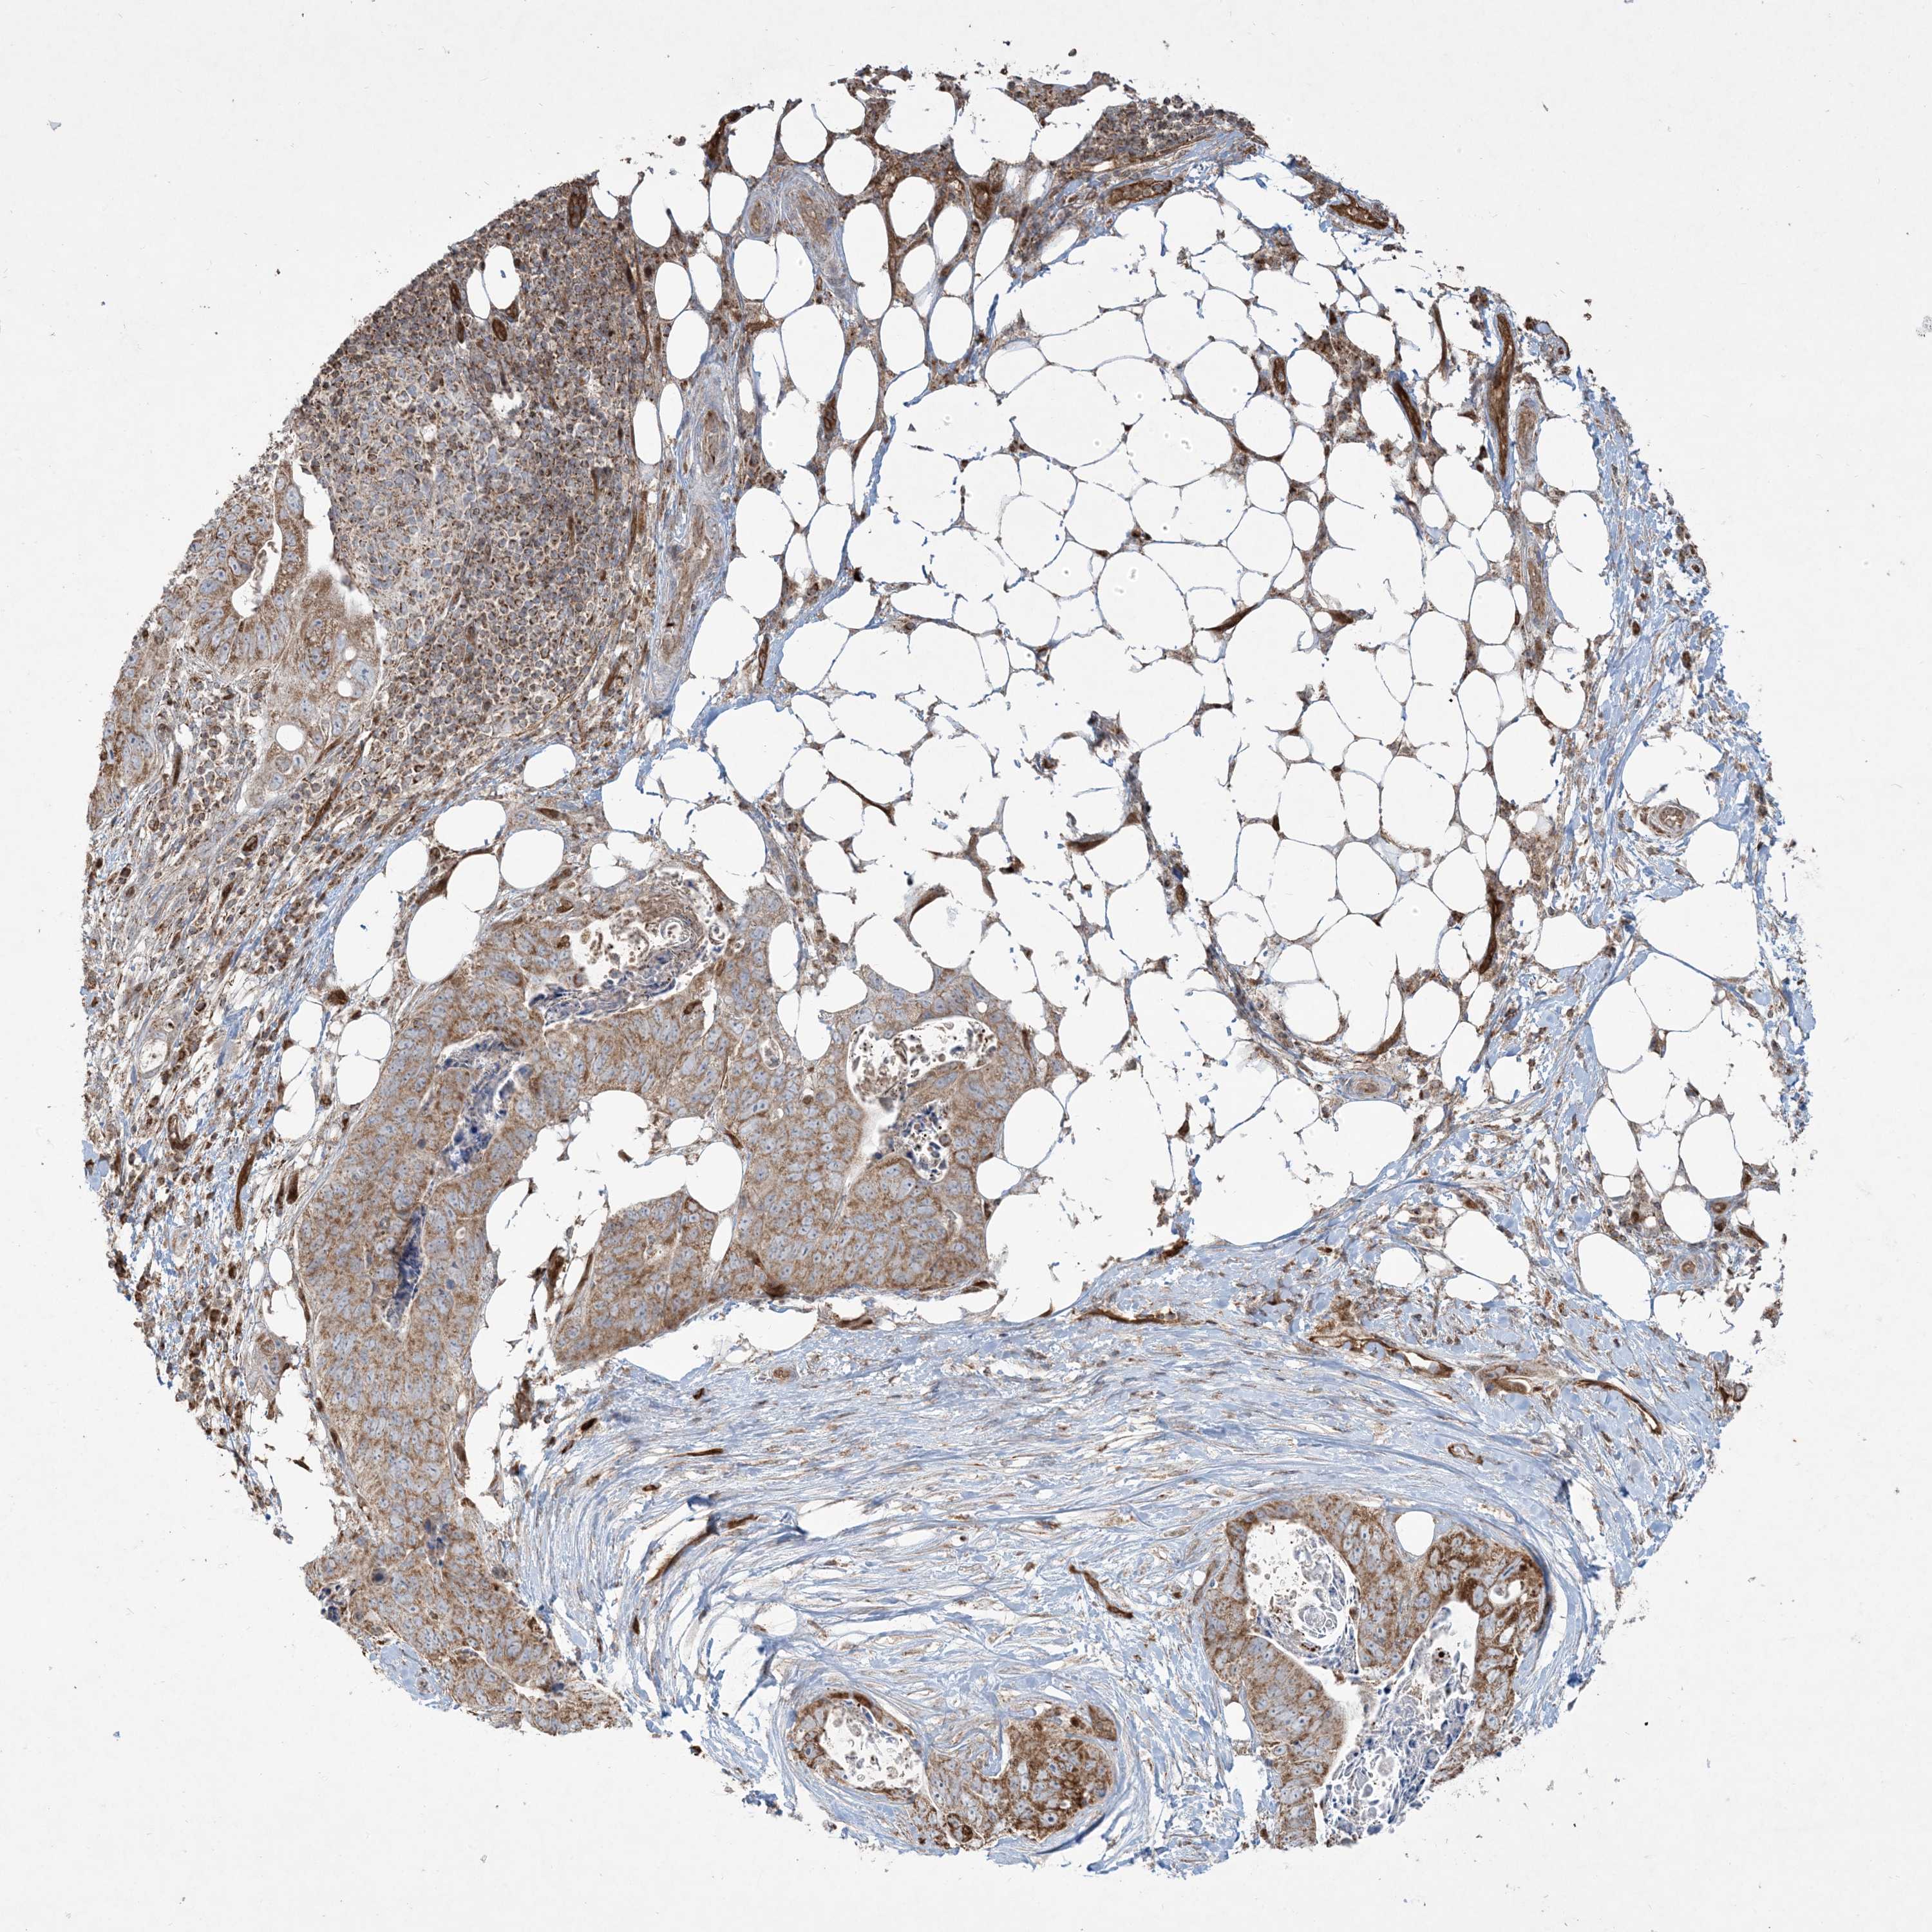

STOMACH CANCER - Protein expressioni

A mouse-over function shows sample information and annotation data. Click on an image to view it in a full screen mode. Samples can be filtered based on level of antibody staining by selecting one or several of the following categories: high, medium, low and not detected. The assay and annotation is described here.

Note that samples used for immunohistochemistry by the Human Protein Atlas do not correspond to samples in the TCGA dataset.

Antibody stainingi

Antibody staining in the annotated cell types in the current human tissue is reported as not detected, low, medium, or high, based on conventional immunohistochemistry profiling in selected tissues. This score is based on the combination of the staining intensity and fraction of stained cells.

Each image is clickable and will lead to virtual microscopy that enables deeper exploration of all samples and also displays staining intensity scores, fraction scores and subcellular localization as well as patient and tissue information for each sample.

Antibody HPA030989

Antibody HPA030990

Staining

High

Medium

Low

Not detected

Intensity

Strong

Moderate

Weak

Negative

Quantity

>75%

75%-25%

<25%

None

Location

Nuclear

Cytoplasmic/membranous

Cytoplasmic/membranous,nuclear

Adenocarcinoma, NOS